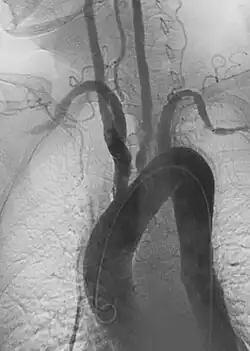

1. Angiography: Sometimes referred to as traditional angiography, catheter angiography or digital subtraction angiography (DSA). A small needle is inserted into a blood vessel, then exchanged for a catheter over a wire. The catheter is directed at the vessel to be studied, and contrast is directly injected to evaluate the lumen under video X-ray. This is an older technique than modern CT angiography or MR angiography, but provides unique advantages. With a catheter in place, provocative maneuvers can be performed such as breath holds or instillation of vasodilators, to evaluate a patient's blood flow dynamically. This can reproduce symptoms and identify functional abnormalities in a vessel that a static CT or MR imaging cannot.[80][81] Angiography provides the basis for all endovascular therapy.

Takayasu arteritis angiography